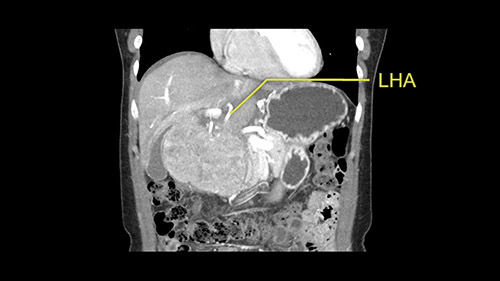

So if we look at the CT scan, on the axial, it’s a larger lesion. It’s about 6 or 7 or 8 centimeters. So it does look a bit threatening in terms of its resectability but if you really drill down deeply into the anatomy, and I think the coronal [imaging] is even better, you can see that the entire mass is on the patient’s left side of the falciform ligament. So it’s really only a left-sided tumor and not even really a left-sided tumor because Segment 4 is uninvolved anatomically.

Some of my colleagues thought it may be involving Segment 4 and we’d need a formal left hepatic lobectomy, dividing anatomically: the left portal vein, left hepatic artery, left bile duct. But I didn’t think so, but you can see there is a challenge in terms of being certain where this tumor is located. So we’re prepared to do any of those 3 but my person view is that its going to be an exophytic tumor off of the left lateral segment and probably a wedge.

As I review the CT scan, we have both arterial and venous phases, the tumor is obvious. But I’ll start by saying that the liver itself does not appear to be cirrhotic to my eye. It’s got a normal contour and allied to that, that I do not see evidence of portal hypertension. The spleen is normal, there’s no collateral vessels. The tumor itself, I measured maximally at about 11 centimetres in diameter and I’m told the alpha fetoprotein is very high (over 10000), which is entirely consistent with this being a solitary hepatocellular carcinoma that is very exophytic. It seems to emanate off the inferior margin of Segment 3 (because that’s the falciform). I’ll start by saying that this is not transplantable. The tumor exceeds our guidelines for transplantation, but it's likely resectable based on normal liver and no portal hypertension.

So the issue with regards to resection. A left sided tumor. I believe I can see the falciform ligament right here so we’re looking at a resection of Segments 2, 3 of the left lobe of the liver. The left portal vein is right there. I think we’ll be wiser to take the left portal vein and therefore get well into Segment 4 and do a left hemihepatectomy. Certainly, one does not need to take the middle hepatic vein; it’s miles from the tumor.

What kind of procedure can we plan for this patient? It obviously has to be a left hemihepatectomy because most of the lesion is actually in Sg4. Can we do something which is less than a hemihepatectomy and just do only a segmental resection? The answer to that is that this vascular supply, if you are trying to ligate only the portal venous pedicle to the Segment 4, it is very close to the tumor and you will end up not having not a great margin as far as tumor resection is concerned so I would recommend a left hemihepatectomy and not just a partial or segmental resection. You can also see that it is crossing the falciform line and going on to Segment 2 and 3 so trying to do anything less than a left hemihepatectomy may not give the right kind of margins which we need for this tumor. Fortunately for us, the contours of the liver, which are very important to see in a Hepatitis B patient, there are no cirrhosis which I can see. The normal liver functions indicate that it's a well compensated Hepatitis B.

The other thing I would do in this case is to certainly to assess the coronal phase as we can see in the coronal phase, this tumor looks like it's growing from Segment 3, and again I don’t think there’s involvement of the right side of the liver or even on Segment 4.